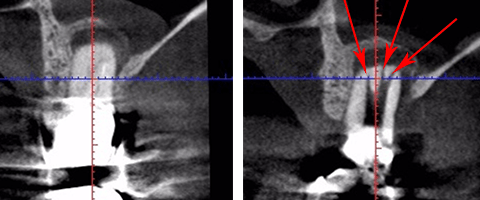

「この歯には、長くて太い金属の土台が入っていて、この金属の土台を取ろうとすると歯が割れてしまうので、治療ができません。なので抜歯です。」

確かに長くて太い金属の土台を除去するのは難しい治療と思います。

ほんの少しでも操作を間違えれば、歯を割ってしまったり歯の根に穴を開けてしまったりします。

地味ーに少しずつ少しずつ金属の土台を削って、少しでも心配ならレントゲンを撮ってと手間暇惜しまずかけて除去したのです。

大阪の根管治療の専門の先生がこの方法を発明しまして、以下の写真の様にマイナスドライバーを2本使ってテコの原理を用い金属の土台を除去します。